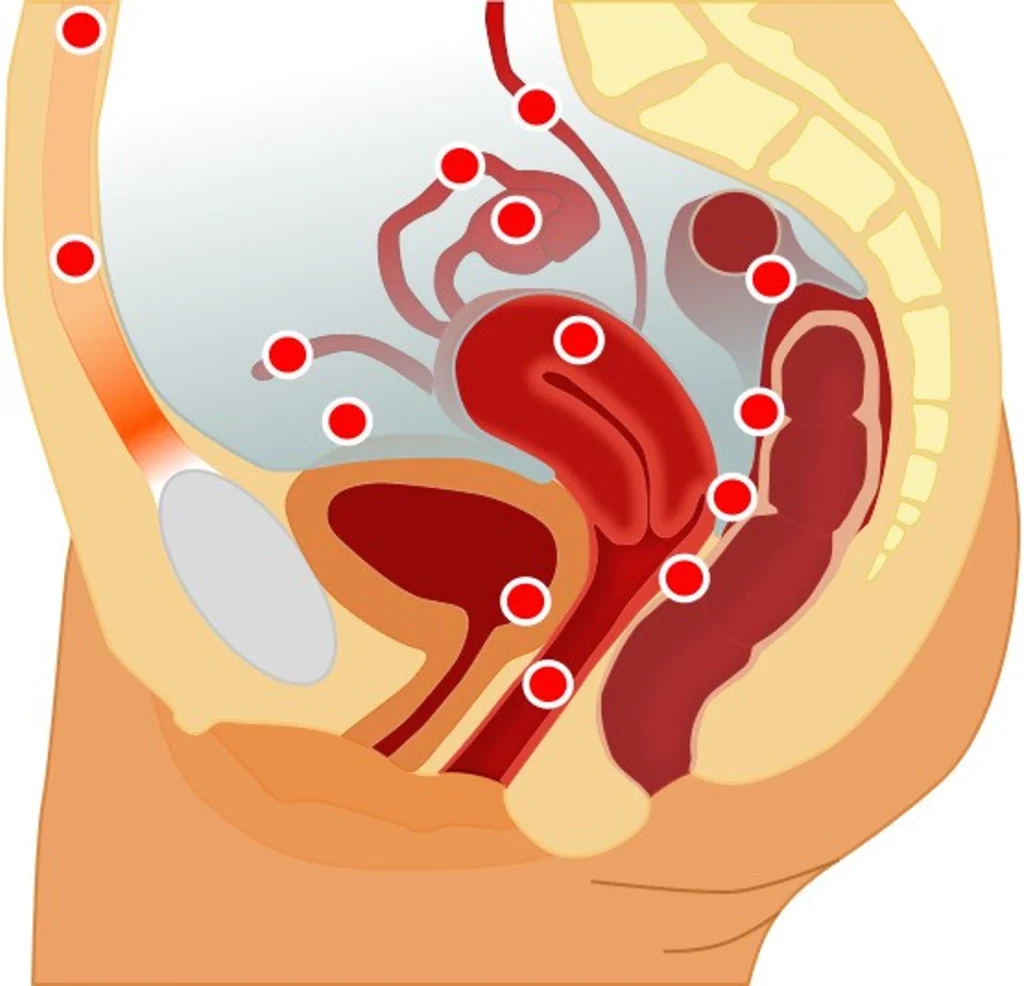

Les zones de migrations du tissu endométrial, qui tapisse normalement la cavité utérine, peuvent être nombreuses et plus ou moins étendues dans la cavité abdominale. Ces migrations provoquent des réactions inflammatoires chroniques très douloureuses, lesquelles impliquent des lésions internes. L’OMS définit 4 types de lésions. La première est qualifiée « d’endométriose superficielle », principalement localisée dans le péritoine pelvien. La deuxième, « l’endométriome » ou « kyste ovarien » est localisée dans les ovaires. Il y a ensuite « l’endométriose profonde », localisée dans le septum recto-vaginal, la vessie et le rectum. Enfin, dans de rares cas, l’endométriose peut migrer hors du bassin, jusque dans les poumons.

Il existe deux principaux types de symptômes. Tout d’abord, il s’agit de douleurs pelviennes, notamment pendant les règles qui sont souvent insupportables et abondantes. Les douleurs peuvent également survenir lors des rapports sexuels. L’endométriose peut également entraîner des dérèglement digestifs et des douleurs lors de l’émission des selles. Outre le facteur douleur, certaines personnes atteintes d’endométriose peuvent être concernées par des problèmes d’infertilité.

Pendant la menstruation, le tissu sanguin de l’endomètre est évacué par le vagin. Or « une majorité de femmes ont des « menstruations rétrogrades », explique le Dr. Kondo. Dans ce cas, le sang et les tissus vont de l’utérus à la cavité pelvienne », notamment vers les trompes de Fallope et les ovaires. Toute personne menstruée peut être touchée sans néanmoins développer d’endométriose. Cependant, l’étude montre que ce paramètre joue un rôle dans l’apparition de facteurs qui peuvent favoriser son développement.